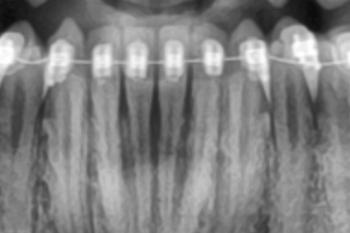

The image shows receded and inflamed gum tissue above the upper front teeth. The gums appear pulled upward, exposing more of the tooth surface near the gumline. There are also signs of redness and irritation, indicating inflammation and possible early infection.

This condition affects the esthetic (smile) zone, making it noticeable and concerning for patients.

This case shows gum recession with signs of inflammation above the upper front teeth. Early dental intervention can stabilize the gums, reduce infection risk, and protect the appearance of the smile.